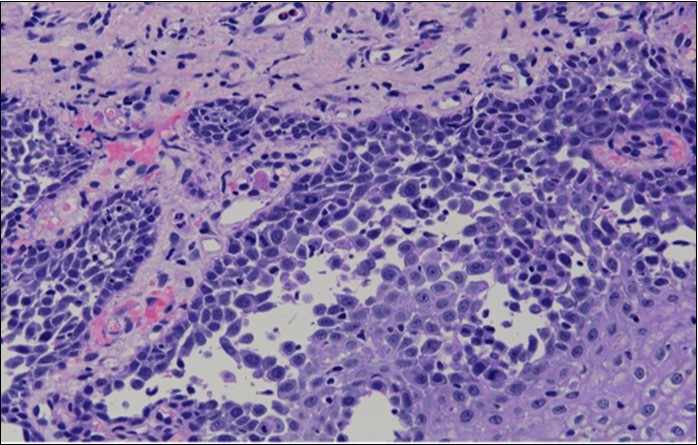

HPV test was negative for high risk subtypes of HPV. The punch biopsy specimen comprised a piece of inflamed cervical tissue in which the transformation zone was represented. The cervical tissue was covered by metaplastic and hyperplastic squamous epithelium showing intraepidermal suprabasal blister formation with acantholysis. Well vascularised dermal papillae lined residual basal cells giving rise to a tombstone appearance were present. There was no evidence of HPV, CIN, CGIN or invasive malignancy.

Figure 4b.Prominent acantholysis identified